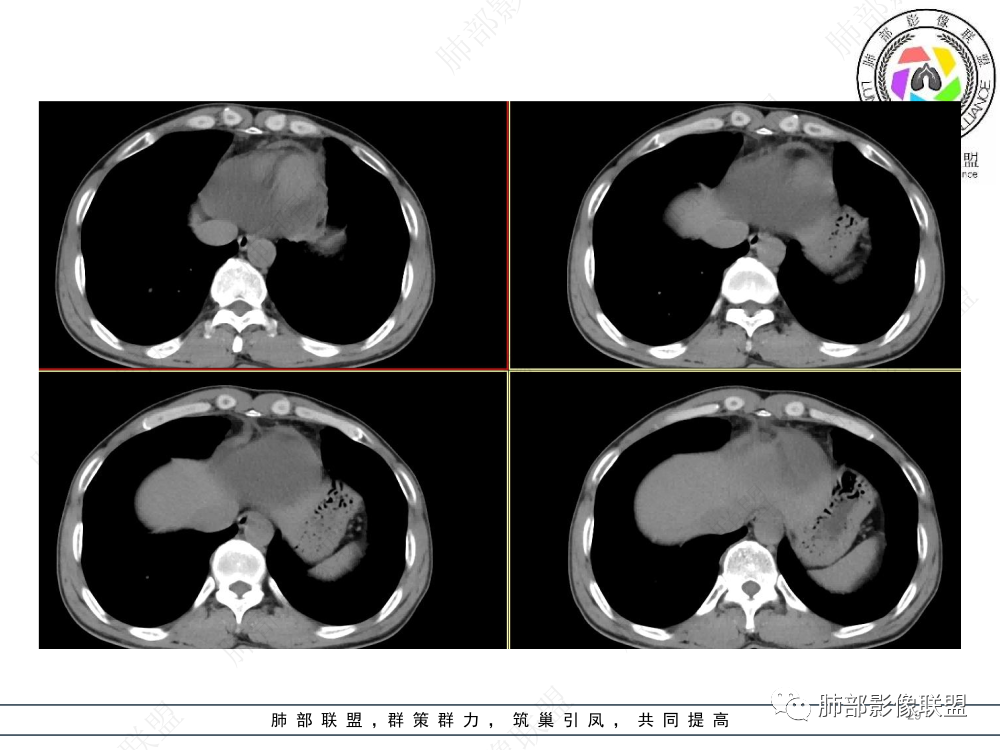

1.临床资料:中老年男性,病史较长-8个月,主诉胸痛,实验室资料:乳酸脱氢酶(LDH)升高。

2.影像表现:前上纵隔较大肿块,密度不均,形态不规则,边界不清,有结节样突起,脂肪间隙显示不清。病灶侵犯左无名静脉及上腔静脉,其中左无名静脉闭塞(胸背部侧支循环明显,亦表明回流受阻)。增强后轻中度不均强化。坏死边界欠清晰。可见心包积液,提示心包受侵犯。右侧上叶及纵隔胸膜下结节影,疑胸膜肺转移可能。胸骨柄后缘皮质不完整,疑骨质破坏(未提供骨窗及矢状位图像)。左锁骨上可见肿大淋巴结。